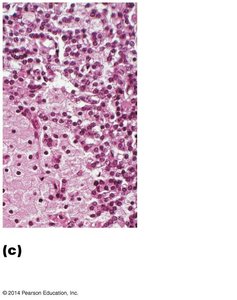

Histology: Contains chief (parathyroid) cells that secrete PTH and oxyphil cells (function unclear).